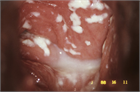

1. カンジダ外陰腟炎の診断は、腟分泌物または外陰皮膚の直接検鏡による菌体の確認、または培養によりカンジダの存在を確認し、臨床症状と併せて診断する。治療は抗真菌薬の局所または内服投与を行い、外陰部にはクリームまたは軟膏を用いる。ただし内服薬は妊婦・授乳婦に禁忌である(推奨度1)